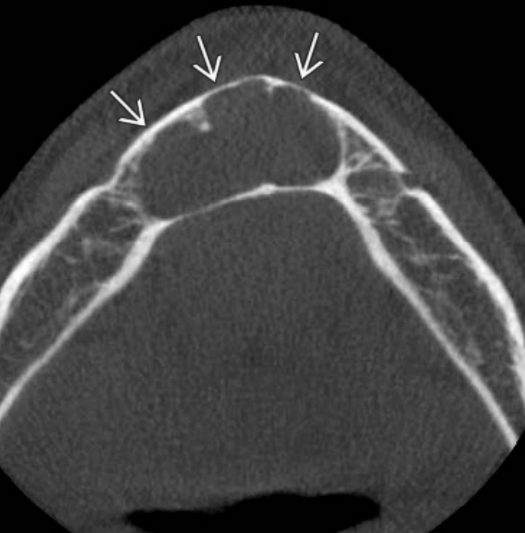

3.1. Ανευρυσματική Οστική Κύστη

Οι κύστεις αυτές είναι ψευδοκύστεις γιατί εμφανίζονται ακτινογραφικά σαν κυστικές βλάβες, μικροσκοπικά όμως δεν έχουν επιθηλιακή επένδυση. Η ανευρυσματική οστική κύστη αντιπροσωπεύει μια καλοήθη οστική βλάβη, η οποία μπορεί να παρουσιαστεί στην άνω ή την κάτω γνάθο, καθώς και σε άλλα οστά. Πιο συγκεκριμένα, εντός του κρανιοπροσωπικού συμπλέγματος, περίπου το 40% των βλαβών αυτών εμφανίζεται στην κάτω γνάθο και το 25% στην άνω.

Κλινικά χαρακτηριστικά

Οι ανευρυσματικές οστικές κύστεις εμφανίζονται τυπικά σε ασθενείς νεότερους των 30 ετών.

Όταν εμπλέκονται η άνω και η κάτω γνάθος, επηρεάζονται συχνότερα οι πλέον οπίσθιες περιοχές. Πόνος αναφέρεται στο ήμισυ περίπου των ασθενών, ενώ μια σκληρή, άσφυγμη διόγκωση αποτελεί κοινό κλινικό σημείο. Κατά την ακρόαση δεν ακούγεται ροή αίματος, ενδεικτικό ότι το αίμα δεν εντοπίζεται εντός ενός αρτηριακού χώρου. Σε έντονη ψηλάφιση μπορεί να παρουσιαστεί κλυδασμός.

Στην περίπτωση που η κύστη επεκτείνεται και στο φατνιακό τμήμα της άνω και της κάτω γνάθου, τα δόντια είναι δυνατόν να παρεκτοπιστούν με ή χωρίς εξωτερική απορρόφηση των ριζών.